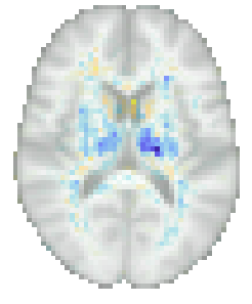

More insight can be gained by examining the proposed method specifically, since it uses disciminative maps that are derived from generative ones. It is worth noting that estimating the generative maps from training data is itself quite stable, since it merely amounts to fitting two basis functions to hundreds of measurements in each voxel (cf. (8)). Furthermore, as illustrated in Fig. 10, the resulting maps are intuitive to interpret, since they show typical age-related effects such as cortical thinning and ventricle enlargement (Fjell et al., 2009; Fjell and Walhovd, 2010). When the discriminative maps are subsequently computed as , however, a strong dependency on the training set size is introduced, because the method explicitly controls the complexity of its noise model in response to the size of the available training set (the bias-variance trade-off of Sec. 4.4). can also capture peculiarities in the data that may be relevant for improving prediction performance, but not for human interpretation. An example of this was shown in Fig. 5, where overall brightness variations and residual MR bias field artifacts were picked up by the noise model. Through , such noise patterns can find their way into , producing hard-to-interpret spatial maps that no longer reflect the expected age-related brain atrophy patterns. This is clearly illustrated in Fig. 4, where the discriminative map is contrasted with the corresponding generative map .

In addition to visualizing its generative maps directly for human interpretation, the causal interpretation of our model can also be used to simulate the effect of aging on actual images. On the population level, this can be achieved by computing age-specific templates for different values of , as illustrated in Fig. 12. More detailed explanations can also be provided at the level of the individual subject, using counterfactuals (Pearl and Mackenzie, 2018) – imaginary images of specific individuals if they had been younger or older. Given an image and the real age , (10) can be used to compute the subject-specific noise vector , which captures the subject’s individual idiosyncrasies that are not explained by the population-level causal model. Counterfactual images can then be obtained by re-assembling the forward model from its constituent components, using a different, imaginary age in (1). Examples of this process are shown in Fig. 13.